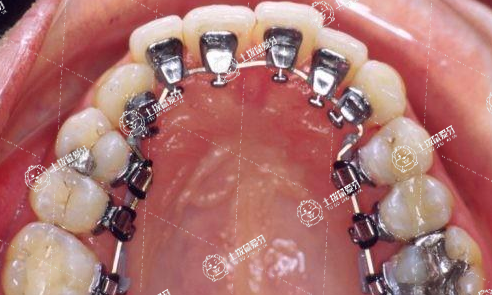

什么是舌側(cè)矯正

舌側(cè)矯正

就是在牙齒內(nèi)側(cè)即靠近舌頭的一面安裝矯治裝置,不用像傳統(tǒng)金屬固定矯正一樣露在外面影響美觀。不過(guò)由于是在內(nèi)側(cè),矯治裝置經(jīng)常與舌頭發(fā)生刮擦,容易反復(fù)引起潰瘍,且不易清潔、操作難度大。

【舌側(cè)矯正技術(shù)優(yōu)勢(shì)】

1、個(gè)性化托槽,量身定制符合個(gè)人牙齒情況的托槽;

2、從美觀上來(lái)看,是完全隱形的矯治器;

3、能矯正各類高難度牙齒畸形病例;

4、不損傷牙面,所以對(duì)牙釉質(zhì)無(wú)損傷;

5、牙齒矯正周期較短,和傳統(tǒng)隱形牙套相比,縮短三分之一的時(shí)間。